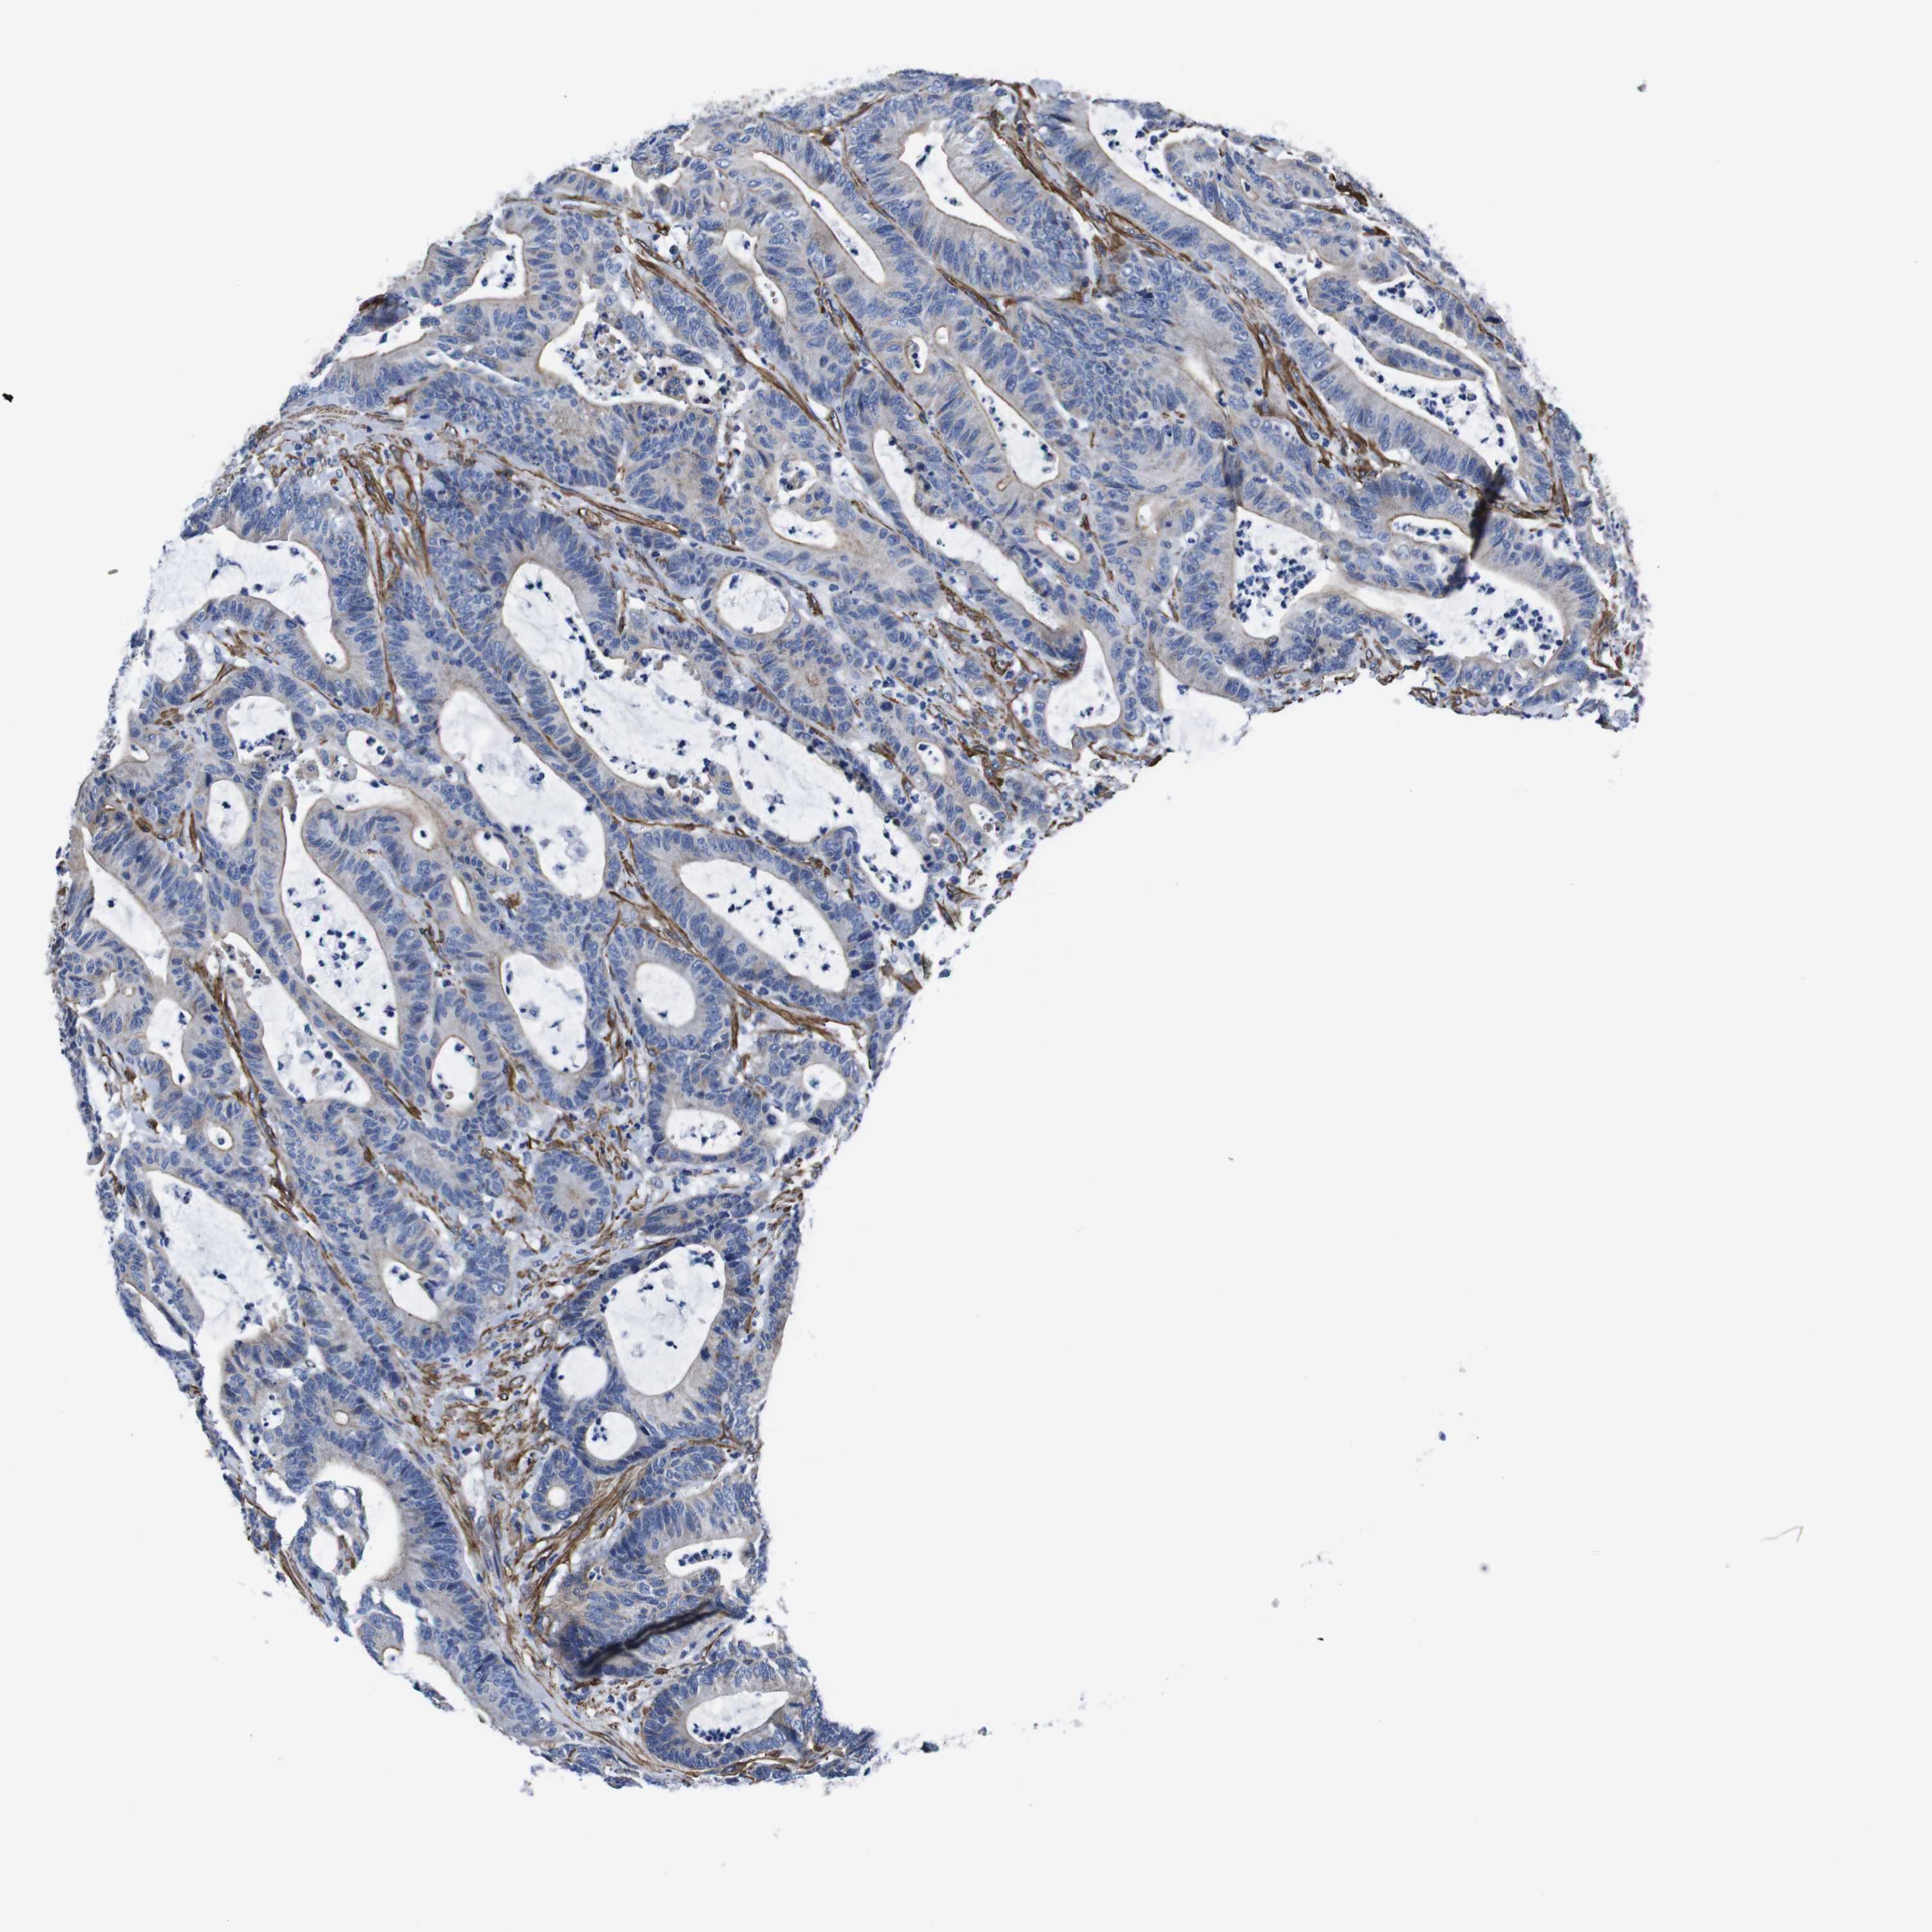

CANCER COLORECTAL CANCER Show tissue menu

Colorectal cancer

Colon adenocarcinoma